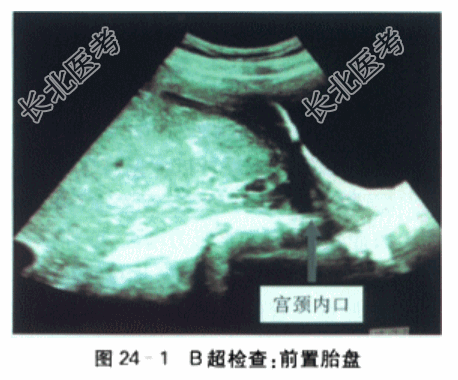

- [材料题] 产妇,25岁,因孕30⁺⁴周,无痛性阴道出血1h余来院就诊。LMP2021-12-29,EDC2022-10-6,停经30天,查尿β-HCG(+),孕2月出现轻微早孕反应(恶心、呕吐),孕5月出现胎动,胎动好,定期于外院做产前检查,2022-6-5外院超声提示单胎,胎盘后壁,胎盘下缘似部分覆盖宫颈内口。今孕妇30⁺⁴周,夜间睡眠中,突发无痛性阴道出血,量约10ml,色鲜红,内裤血迹晕染呈淡红色。遂至外院急诊,病程记录当时查体“未及宫缩,血水打湿内裤,色鲜红,阴道窥积检查:胎膜似已破,宫口未开,阴道内有中等量鲜红色血水,膝反射存在”,遂予安宝100mg,20滴/min静滴保胎,因孕妇及家属要求转上级医院,联系120后送至我院急诊,查外阴见少量血迹,阴道内未见明显血性液体流出,未及宫缩。孕妇否认外伤史,否认近期性生活史,为进一步治疗,急诊拟“G₁P₀,孕30⁺⁴周,前置胎盘,胎膜早破?”收治入院。患者近期精神可,睡眠一般,食欲佳,二便正常。无外伤手术史,无高血压心、肺、肝、肾等重大脏器疾病史。生育史0-0-0-0,平素月经规则157/30,量中,无痛经。体格检查:入院查体:营养中等,无贫血貌,水肿(-),T37.0℃,P100次/min,R20次/min,BP110mmHg/70mmHg;Ht1.60m。Wt65kg,下肢无水肿,心律齐,有力,各瓣膜听诊区未闻及杂音;双肺呼吸音清,未闻及干湿啰音;肝脾未触及,腹膨隆,神经系统(-)。产科检查:腹膨隆,胎位LOA,胎动好;未及明显宫缩,子宫张力不高,腹围96cm,宫高26cm,胎心145次/min,胎头高浮。实验室检查:A型血,RH血型阳性,抗体筛选:阴性;PT9.20s,APTT25.4s;Fg5.11g;D-二聚体0.25mg/L;纤维蛋白(原)降解产物2.70mg/L。输血前测试HCV-AB-IgG(-)0.01S/CO,TP-Ab(-)0.12S/CO,ALT15IU/LHBsAg(-)0.01IU/ml,HBsAb(+)157.42mIU/ml,HBeAg(-)0.344S/CO,HBeAb(+)0.15S/CO,HBcAb(+)9.84S/CO。血常规:CRP8mg/L,WBC8.57×10⁹/L,N85.0%,RBC3.29×10¹²/L,Hb98g/L,PCV30.2%,PLT174.00×10⁹/L。肝肾功能,尿液检查,梅毒和艾滋病实验室检查均为(-)。ECG:TⅢ倒置,aVF双相。影像学检查:B超检查:双顶径75mm,头围292mm,股骨长59mm,腹围长266mm。胎盘位置:后壁。胎盘分级:Ⅱ~Ⅲ级,胎盘主体位于子宫下段,边缘完全覆盖宫颈内口(红色箭头处)(见图24-1)。胎心测及,最大羊水池深度:60mm。脐动脉血流:S/D2.3,RI0.6,PI0.8。宫颈管长度40mm。单胎横位中央性前置胎盘EFW1660g。MRI:前置胎盘未见明显胎盘植入现象。